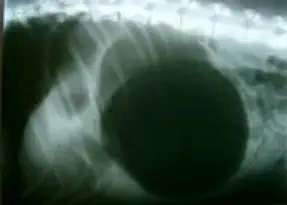

Bestehen Sie in diesem Fall immer auf einer Röntgenaufnahme des Unterleibs. Ein verdrehter Bauch ist darauf immer deutlich als schwarzer Ballon zu sehen.

Eine Magendrehung mit einer damit verbundenen Verschlechterung der Magenwand aufgrund einer verminderten Durchblutung